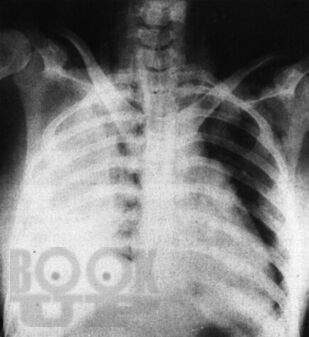

Во втором издании руководства под редакцией С. П. Л. Трэвиса отражены современные представления о болезнях органов пищеварения, их диагностике и лечении. Обращает на себя внимание легкая для восприятия структура издания, каждая из глав которого посвящена заболеваниям какого-либо органа желудочно-кишечного тракта. В отдельной главе изложены особенности питания при гастро-энтерологических заболеваниях, где наряду с традиционными диетическими рекомендациями большое внимание уделено вопросам энтерального и парентерального питания. Особый интерес представляют алгоритмы обследования и лечения, рекомендуемые при различных патологических состояниях системы пищеварения. Книга хорошо иллюстрирована и включает справочные сведения по лабораторной диагностике и фармакотерапии заболеваний желудочно-кишечного тракта.